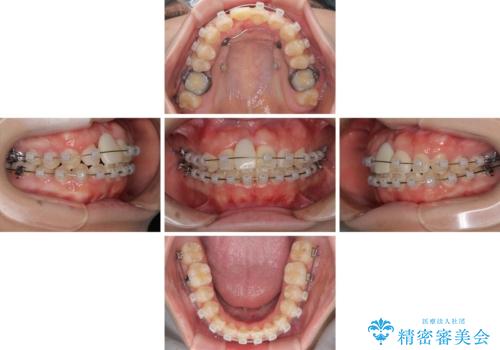

- 矯正装置

- クリアブラケット

- 治療期間

- 2年1ヶ月

- 治療回数

- 10-30回